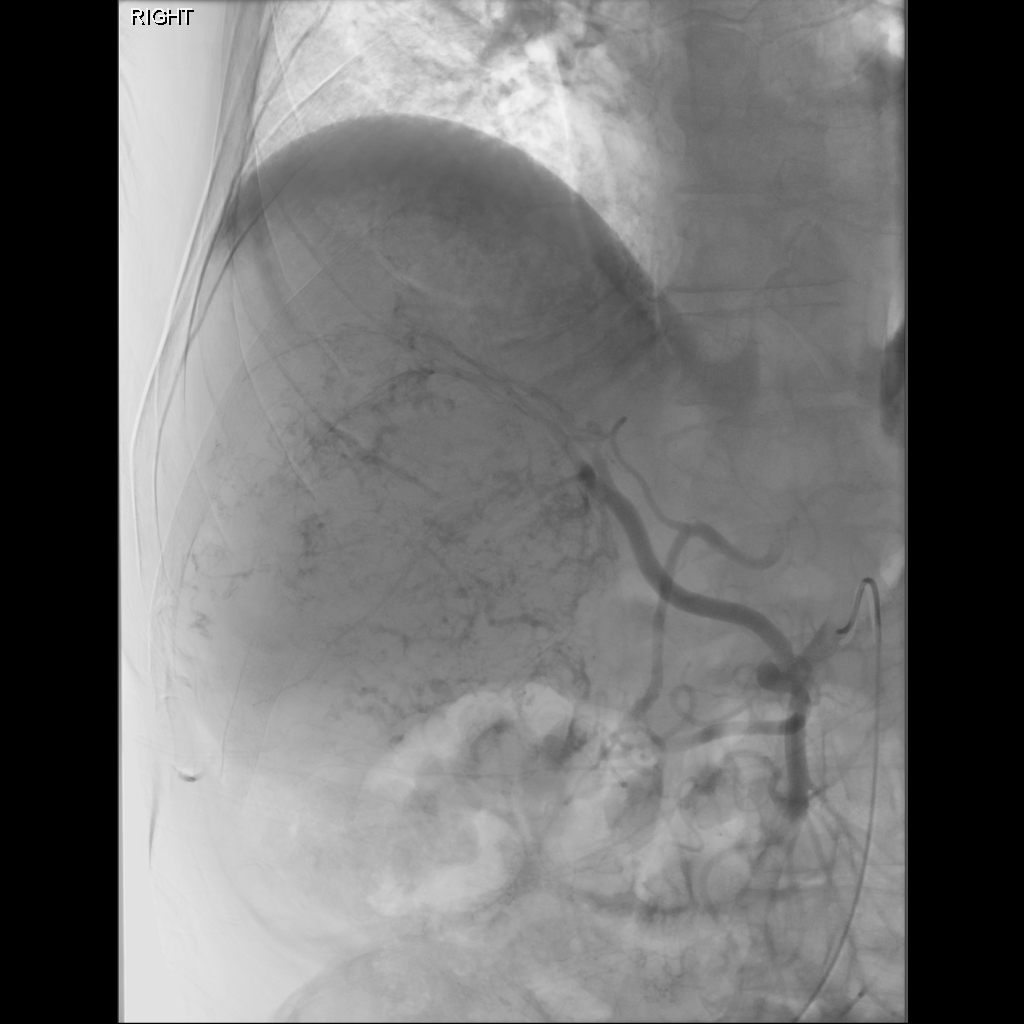

Mapping Angiogram

Comprehensive vascular mapping with CBCT to identify tumor supply and prevent extrahepatic deposition.

• Selective catherization

• Identify variant hepatic arterial anatomy

• Coil embolization of gastroduodenal or right gastric artery

• MAA injection to estimate lung shunt and dosimetry